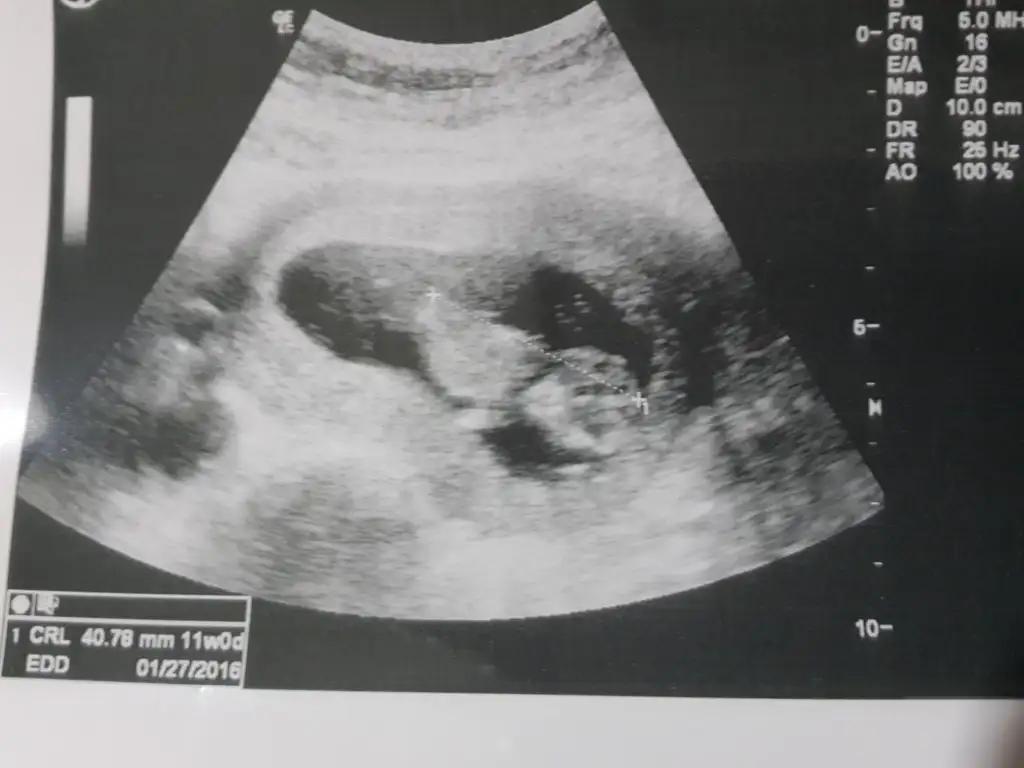

ayy demek belli cinsiyeti maaşallah :) tabii zayıflık da etkiler muhakkak, hiç düşünmemiştim bu durumu .. ben de ortalamalara göre zayıfım yani öyle kemiklerim sayılacak gibi değil ama... bakalım biz de bugün 12 haftamıza girdik önümüzdeki hafta 2li testte inşallah doktorumuz cinsiyet hakkında ipucu verir :)canım benim erkek, bir de zayıf olanlar daha cabuk hissediyorlarmış, ben ondan da şüphelendim, asırı zayıfım yağ dokum hiç yok